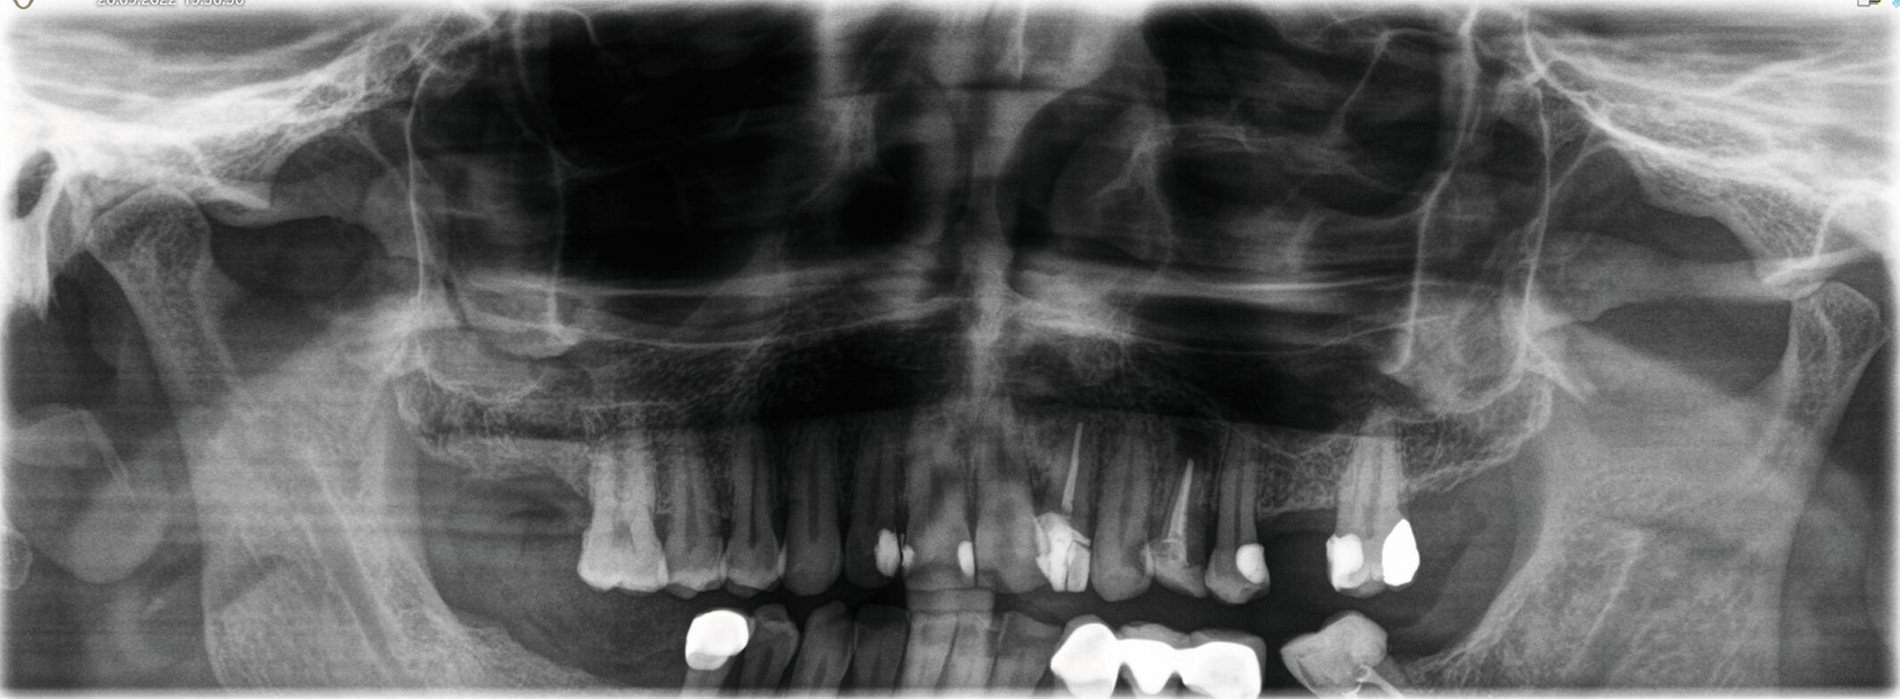

Die pathologische Untersuchung bestätigte die klinische Diagnose durch das Vorhandensein einer respiratorischen Schleimhaut beziehungsweise eines Epithels. Der Defekt wurde mit einer Membran gedeckt, die Wunde dicht vernäht. Zur Kontrolle nach der Wurzelresektion und den Zystektomien wurde ein OPG angefertigt (Abbildung 5). Der Patient erhielt für fünf Tage eine Antibiose. Darüber hinaus wurden Nasentropfen verschrieben und ein Schnäuzverbot erteilt.